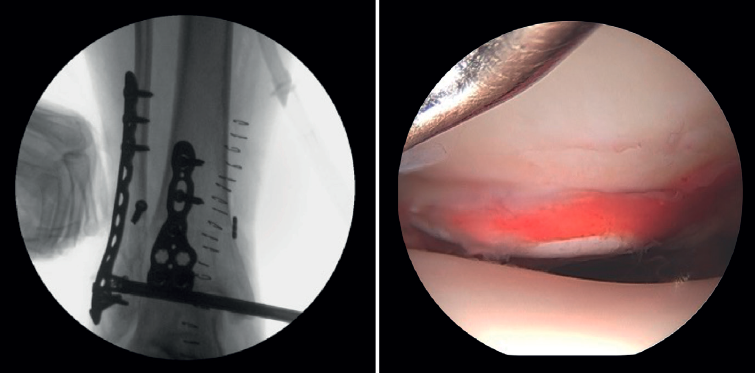

Xie showed that stabilization of the syndesmosis with a dynamic fixation system offers equivalent functional results and fewer complications compared to screw fixation(28). AAORIF allows the evaluation of joint congruency after anatomical reduction of both the posterior and anterior syndesmosis. It also allows assessment of the overcorrection that can result from over-compression of the tibiofibular mortise, which has been shown to be highly arthrogenic(29). During reduction of the syndesmosis, help is provided by a palpation probe which we should be able to insert once the syndesmosis has been fixed.

AAORIF during ankle fracture fixation may improve the detection and treatment of syndesmosis instability. Liu, in a cadaveric model, found arthroscopy to be very sensitive in detecting sagittal and external rotation instability of the syndesmosis in the early stages of the injury, even with the application of low forces. More than twice as many patients with Weber type B or C fractures were seen to have arthroscopically detected instability of the syndesmosis (66%) compared to injuries detected by stress radiography (30.2%). The conclusion was that arthroscopy allows better determination of instability in multiple planes (sagittal and rotational) than fluoroscopy alone(5,21,30).